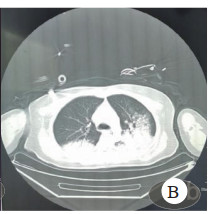

头胸部CT(图 3、图 4),分别提示右侧小脑半球、右侧枕叶片状低密度影,局灶性脑水肿以及双肺多叶段片状模糊影及磨玻璃影。

| 图 4 胸部CT Fig 4 Chest CT |